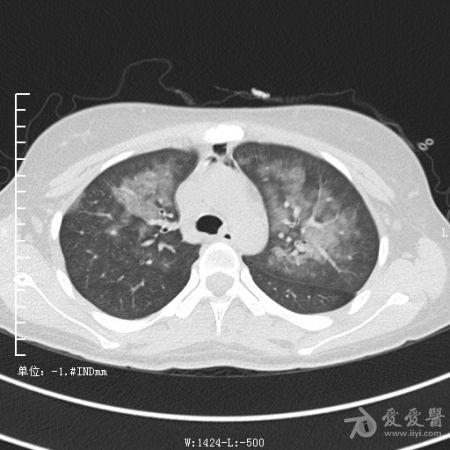

典型支气管扩张及肺水肿CT片

典型支气管扩张肺水肿